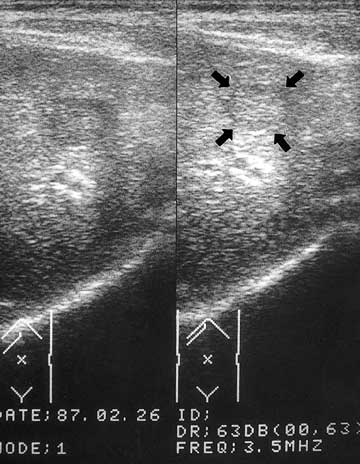

![]() 59歳、男性の腹部超音波検査。肝臓内に約2X3?の肝がんが |